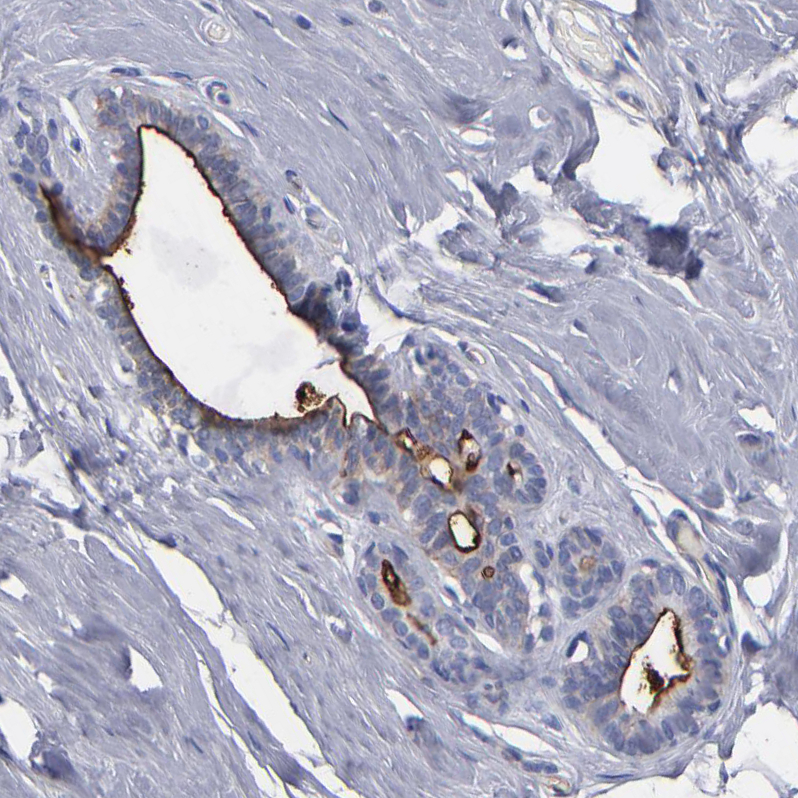

Immunohistochemical staining of human Ovarian cancer shows strong positivity in tumor cells.